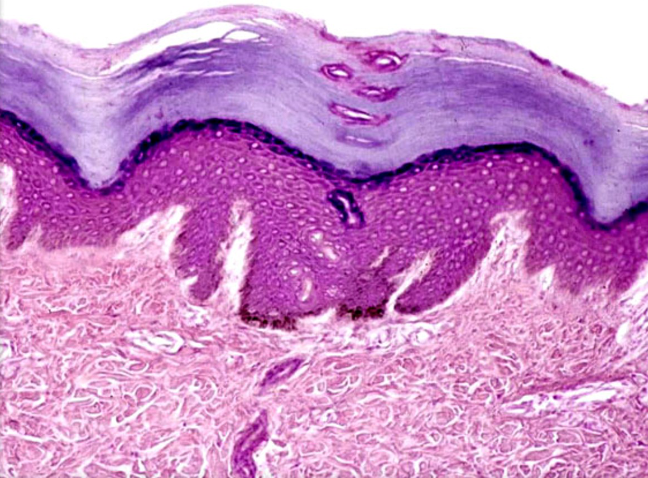

Stratified squamous epithelium (nonkeratinized)

A type of epithelial tissue composed of multiple layers of cells, with the outermost layer remaining moist. It is found lining body cavities and organs such as the mouth, esophagus, and vagina.

<p>A type of epithelial tissue composed of multiple layers of cells, with the outermost layer remaining moist. It is found lining body cavities and organs such as the mouth, esophagus, and vagina. </p>

Epidermis

The outermost layer of skin, composed of stratified squamous epithelium that provides a protective barrier against environmental factors.

<p>The outermost layer of skin, composed of stratified squamous epithelium that provides a protective barrier against environmental factors. </p>

Dermis

The layer of skin located beneath the epidermis, consisting of connective tissue that provides strength and elasticity, containing blood vessels, nerves, and hair follicles.

<p>The layer of skin located beneath the epidermis, consisting of connective tissue that provides strength and elasticity, containing blood vessels, nerves, and hair follicles. </p>

Hypodermis

The deepest layer of skin, also known as subcutaneous tissue, composed of loose connective tissue and fat, providing insulation and cushioning for underlying structures.

<p>The deepest layer of skin, also known as subcutaneous tissue, composed of loose connective tissue and fat, providing insulation and cushioning for underlying structures. </p>